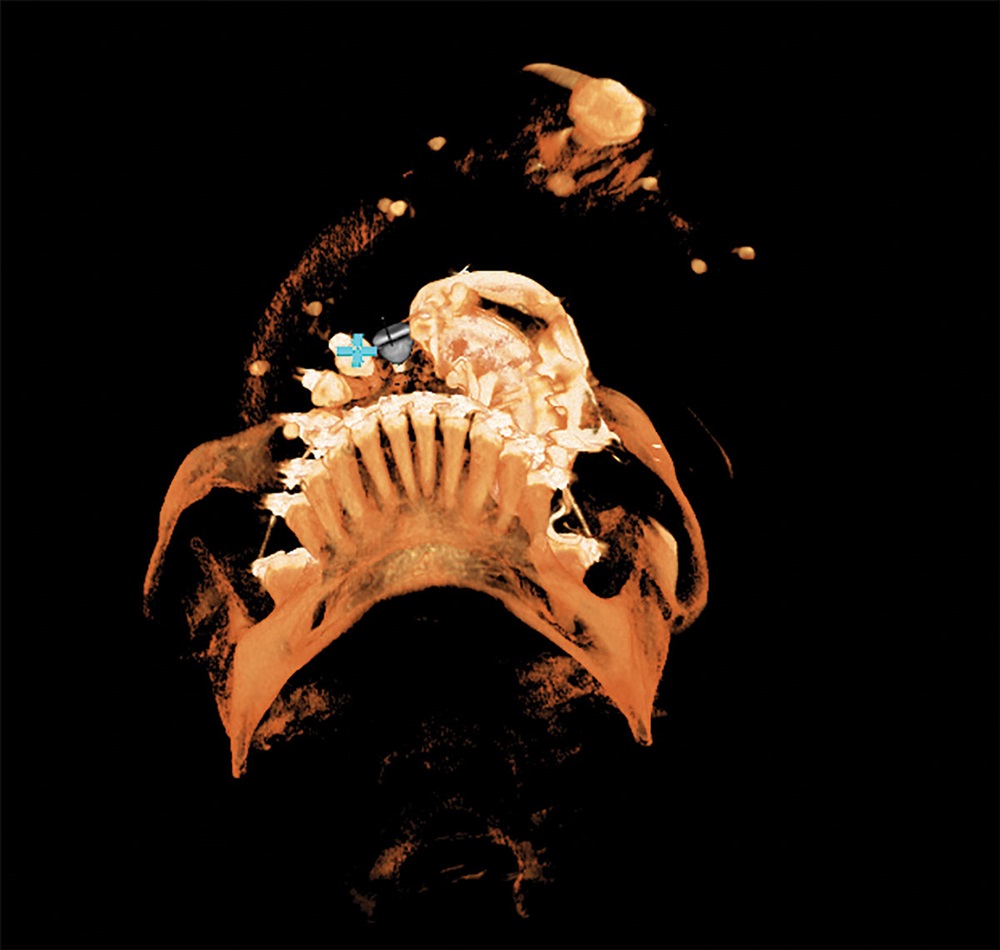

Recently, I placed three implants in Teeth 3, 4 and 5 in conjunction with a sinus lift. Implants in such close proximity to one another can be a challenge even for a specialist. By using the preplanning software, I virtually placed the implants precisely where I wanted them to go, as shown in Figs. 7, 8 and 9. I was thrilled with the outcome. As you can see on the X-ray in Fig. 10, the implants were placed precisely according to the plan.

Fig. 7: 3D plan for Case 1 shows rendering with bone.